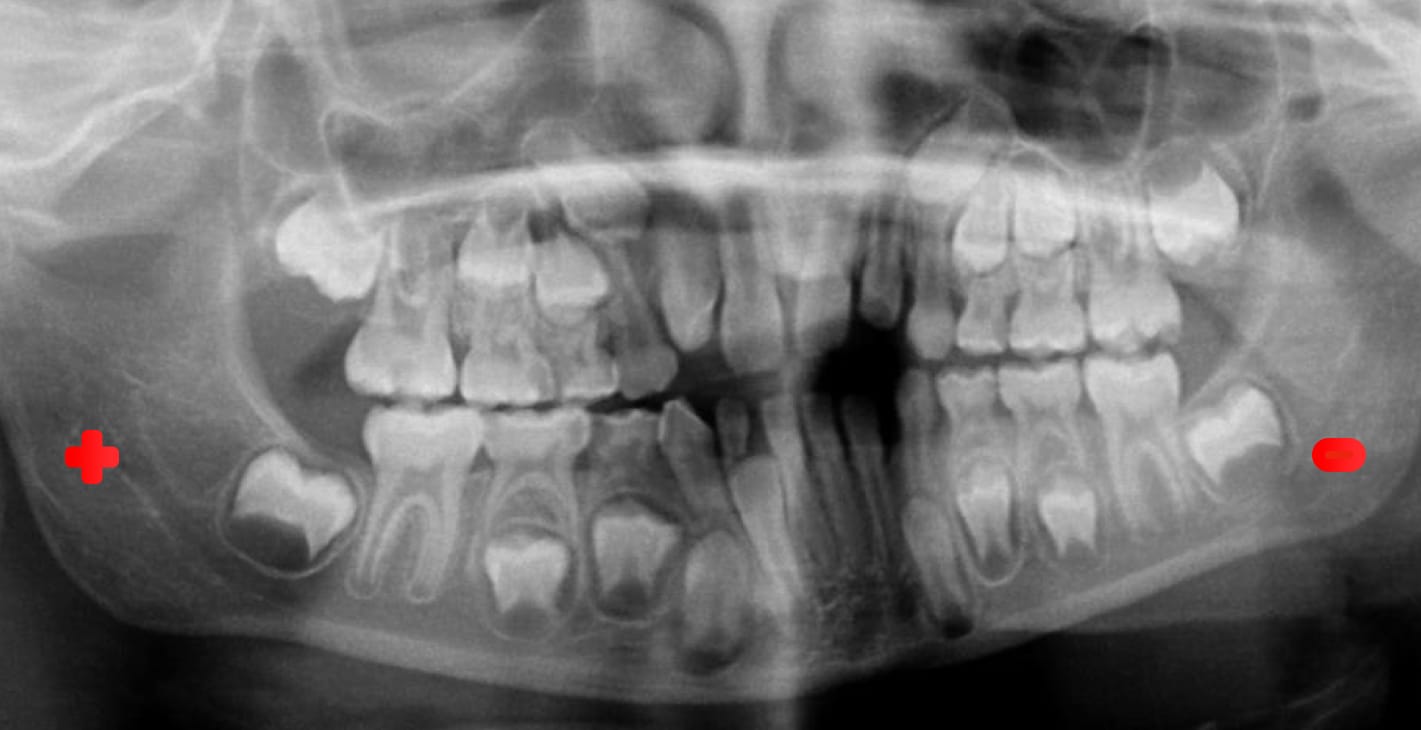

The orthopantomography (OPG), also called panoramic radiography, is a widely used extraoral radiographic technique and great diagnostic utility in the dental clinic, since it allows the visualization of elements that could not be seen with conventional intraoral or extraoral techniques.

The orthopantomography is a radiological technique used in dentistry, especially in orthodontics, which allows obtaining a complete panoramic image of the teeth, mandible and maxilla. It is performed using special equipment called orthopantomograph, which can be conventional or digital. This equipment is essential for diagnosis in the dental clinic, and is widely used in oral surgery, implantology, orthodontics, periodontics, and oral pathology.

- Evaluation of patterns of tooth eruption, growth and development.

For the technique to be considered acceptable, a panoramic radiography should clearly show the following anatomical structures:

- Teeth: The dentition should show a smooth curve at the smile line, with an easily distinguishable gap between the upper and lower teeth. The posterior teeth should be of normal size and there should not be excessive overlap between the premolars. The apices of the anterior teeth must be complete and the crowns must be visible on the radiographic image.